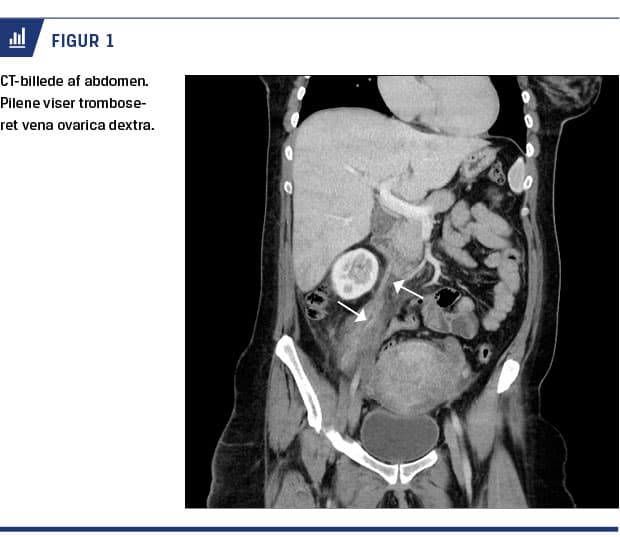

Klinisk havde man mistanke om appendicitis, og man bestilte derfor CT af abdomen (Figur 1). Denne viste inflammatoriske forandringer, der udgik fra venstre side af uterus og op til nedre højre nyrepol samt en tromboseret højresidig ovarievene.

Patienten i sygehistorien havde flere risikofaktorer for tromboemboli post partum, og på trods af profylaktisk trombosebehandling udviklede hun POVT. Diagnosen blev stillet på baggrund af billeddiagnostik, og en CT viste en tydelig tromboseret højre ovarievene (Figur 1).